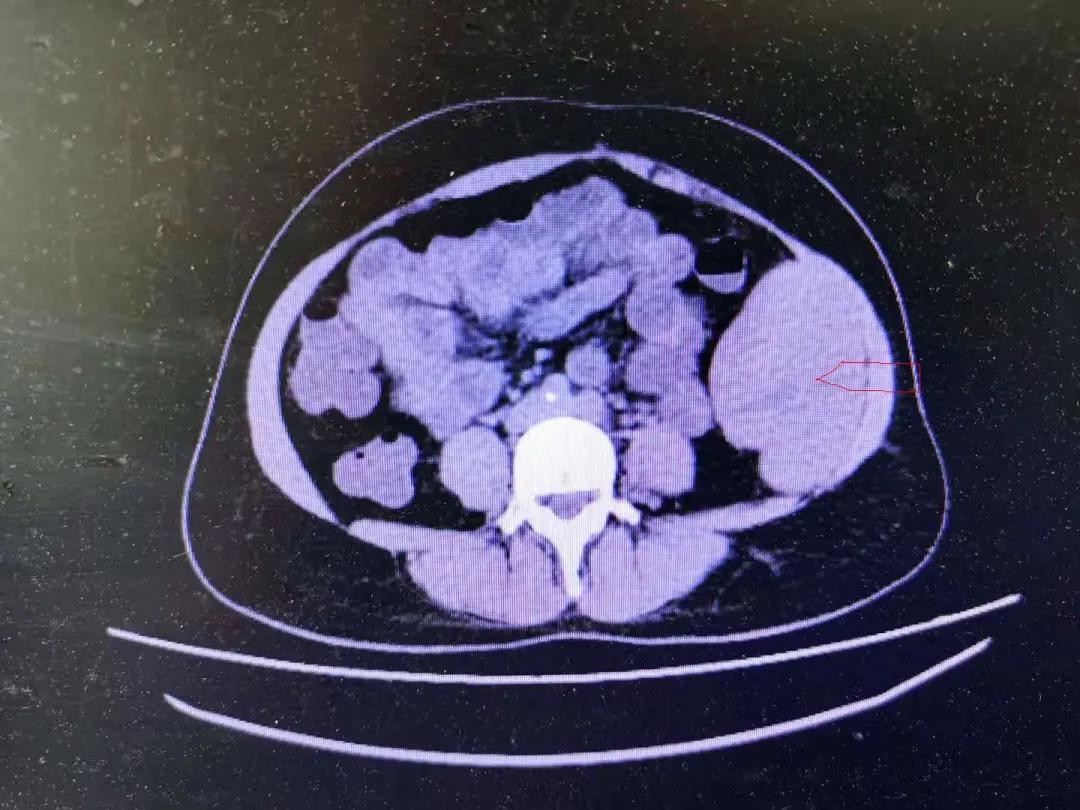

平行CT

2

患者女性,37岁,因“发现左侧腹部包块2月”入院,既往有“剖宫产史”。入院查体可见腹部平坦,下腹部陈旧性手术疤痕,腹软,左侧腹部可触及质硬包块,有压痛、无反跳痛,直径约10*6cm,边界欠清,活动度差。腹部超声示左侧腹腔低回声包块,114*90*54mm,边界尚清,形态欠规则,回声不均匀;腹部CT示左侧中腹部腹腔巨块状软组织密度影,分叶改变,6.4*8.6*9.5cm,腹膜后结构清晰,无肿大淋巴结。入院后行肿瘤标记物及结肠镜等检查结果无明显异常,术前分别请泌尿外科及妇科会诊,基本排除泌尿肿瘤及妇科肿瘤的可能性。